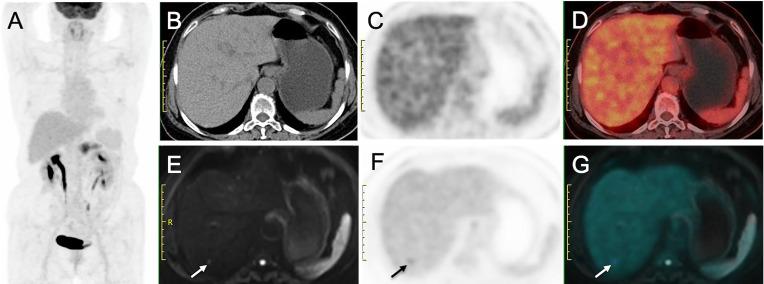

The diagnostic performance of FDG PET/CT plus delayed PET/MR imaging was not significantly different from that of CE-CT/MR imaging in the assessment of tumor resectability [area under the receiver operating characteristic curve: 0.927 vs. 0.925 ( = 0.975)], N stage (accuracy: 80% (16 of 20 patients) vs. 55% (11 of 20 patients), = 0.125), and M stage (accuracy: 100% (40 of 40 patients) vs. 93% (37 of 40 patients), = 0.250). Moreover, 14 of 40 patients had liver metastases. The number of liver metastases detected by CE-CT/MR imaging, PET/CT, and PET/MR imaging were 33, 18, and 61, respectively. Compared with CE-CT/MR imaging, PET/MR imaging resulted in additional findings of more liver metastases in 9/14 patients, of which 3 patients were upstaged. Compared with PET/CT, PET/MR imaging resulted in additional findings of more liver metastases in 12/14 patients, of which 6 patients were upstaged.

Although FDG PET/CT plus delayed PET/MR imaging showed a diagnostic performance similar to that of CE-CT/MR imaging in the pretherapeutic assessment of the resectability and staging of pancreatic tumors, it still has potential as the more efficient and reasonable work-up approach for the additional value of metastatic information provided by delayed PET/MR imaging.